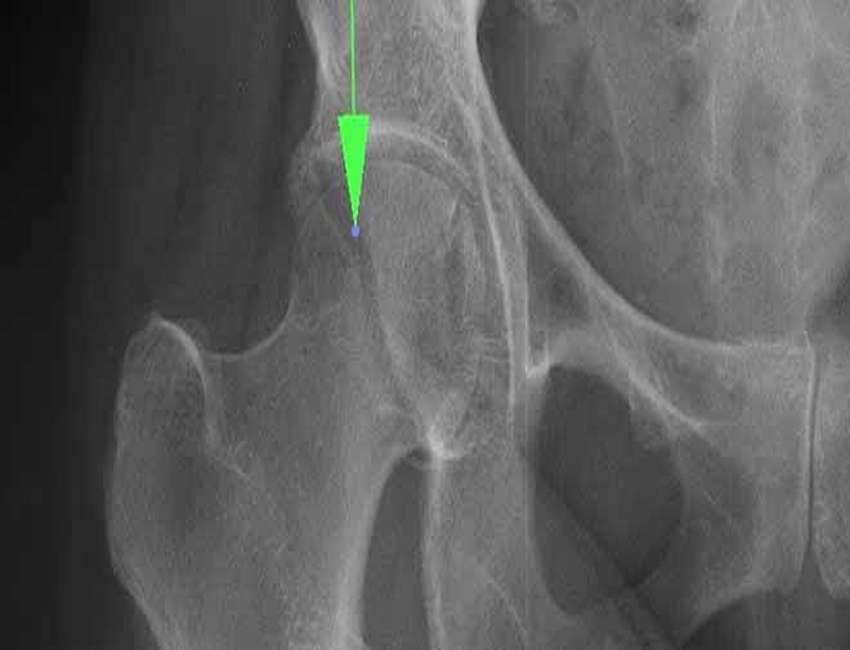

• اهمیت تشخیص دقیق

تشخیص نوع شکستگی از طریق رادیوگرافی و گاهی MRI انجام می‌شود. تشخیص دقیق به جراح اجازه می‌دهد بهترین روش جراحی یا درمان غیرجراحی را انتخاب کند.

پیگیری رادیوگرافی

پیگیری‌های تصویربرداری پس از عمل جراحی، نقش کلیدی در بررسی تثبیت شکستگی و روند جوش خوردن استخوان دارد.

این رادیوگرافی‌ها به جراح اجازه می‌دهند در صورت نیاز، تصمیمات اصلاحی بگیرد یا زمان شروع توانبخشی فعال را تعیین کند.

معمولا اولین تصویر رادیولوژی چند هفته پس از عمل گرفته می‌شود و پیگیری‌های بعدی طی ماه‌های بعد انجام می‌شوند تا اطمینان حاصل شود که استخوان به درستی بهبود یافته و مفصل عملکرد خود را حفظ می‌کند.